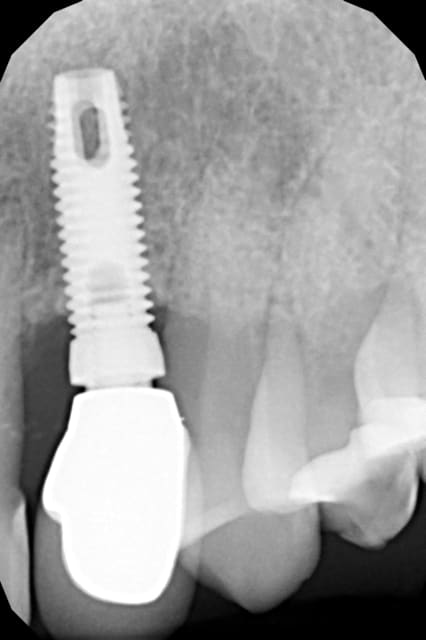

implant et pilier lousse

couronne cimentée sur pilier

le pilier est mobile, dévissage

il semble que ce soit un hex externe de type Nobel

que faites-vous et quel est l'implant d'après vous

NOBEL SELF TAPING 3.75mmn mais le col semble plus haut, existait-il différent hauteur de col pour ces implants?

pose de l'implant en 1998